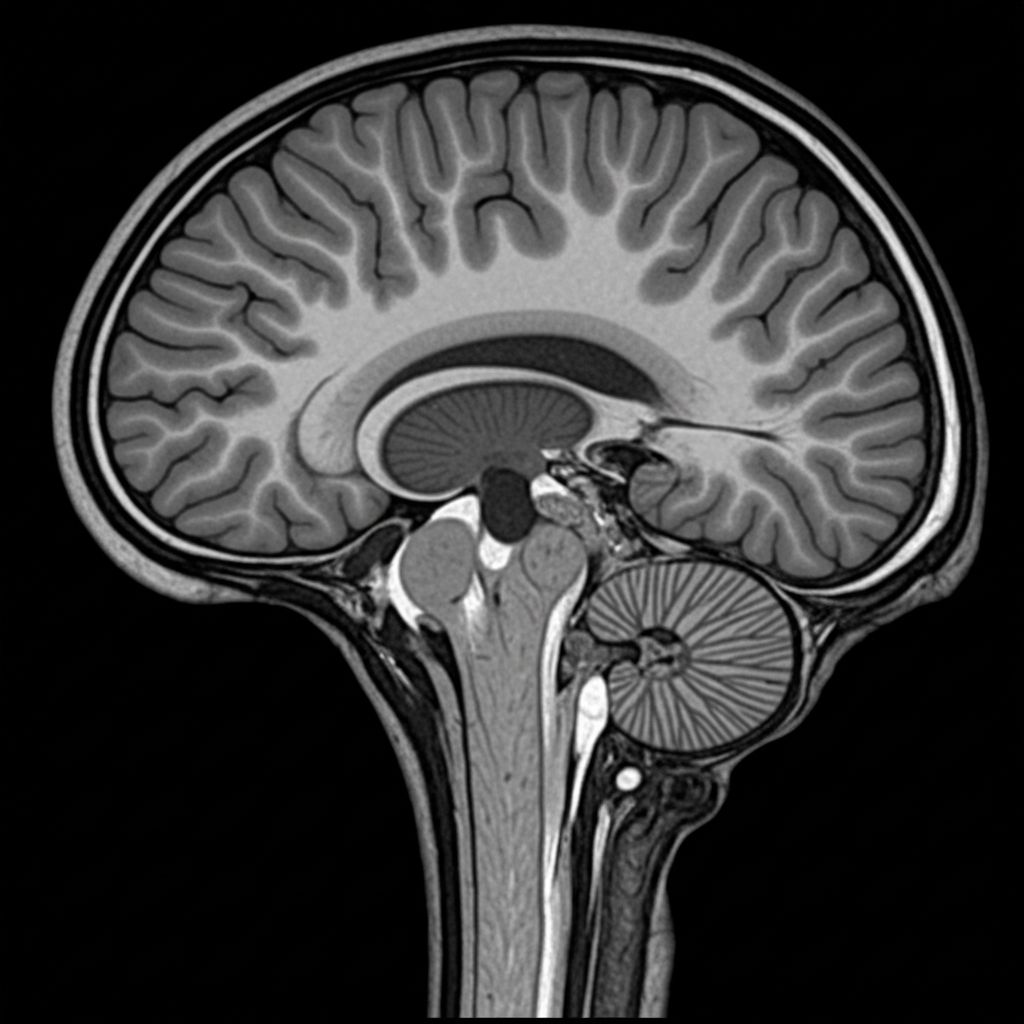

Die Aufmerksamkeitsdefizit-/Hyperaktivitätsstörung ist eine neurobiologische Erkrankung, die durch Veränderungen im Dopamin- und Noradrenalin-Stoffwechsel des Gehirns gekennzeichnet ist.

Bei ADHS liegt eine Störung im Dopamin- und Noradrenalin-System vor, die die Signalübertragung zwischen den Hirnregionen beeinträchtigt.

Als spezialisierte neurologische Privatpraxis bieten wir Ihnen eine umfassende, wissenschaftlich fundierte ADHS-Diagnostik nach aktuellsten S3-Leitlinien. Unsere erfahrenen Fachärzte für Neurologie und Psychiatrie nutzen modernste neuropsychologische Testverfahren, computergestützte Aufmerksamkeitstests und bildgebende Diagnostik.

Der Diagnostikprozess umfasst eine ausführliche Anamnese, standardisierte Fragebögen, neuropsychologische Testbatterie sowie bei Bedarf EEG-Untersuchungen. Wir nehmen uns Zeit für eine sorgfältige Differentialdiagnostik, um andere Erkrankungen mit ähnlichen Symptomen auszuschließen und Ihnen eine präzise Diagnose zu ermöglichen.